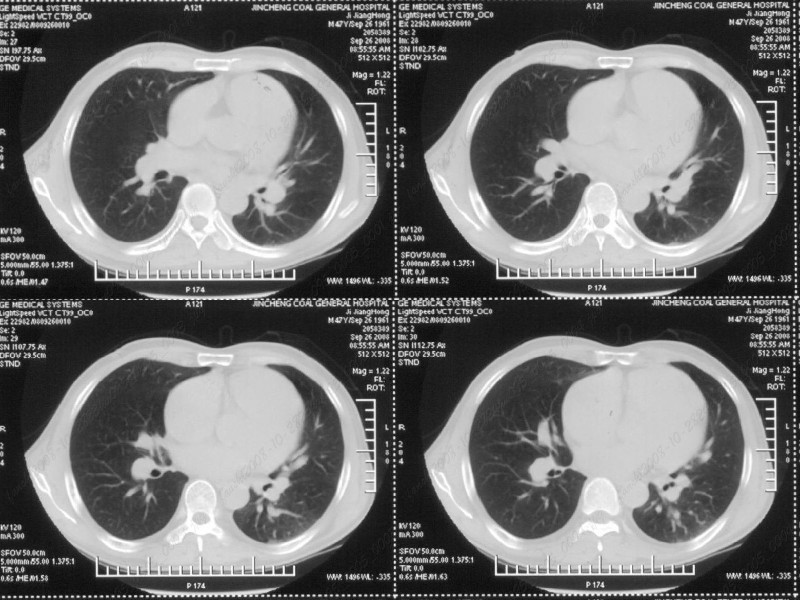

男性,47岁。胸部不适一年,ct检查发现右胸膜下结节。http://www.radida.com/bbs/forum.php?mod=viewthread&tid=46094

右下肺前胸膜下小结节,强化不明显。建议定期观察!

病灶周围似有纤维化征像,增强明显强化,但中央可见点状低强化区,考虑慢性病变可能如炎性假瘤等,病灶边缘部分毛糙有切迹,双侧胸腔少量积液影,不除外恶性

右肺中叶外侧段胸膜下结节状病灶,性质待定(不排除周围型肺癌可能)。

右前胸膜下小结节,边缘有小纤维条索影与胸膜粘连,考虑如炎性假瘤之类慢性病变可能。期待二周后的结果。

汇报临床诊断:右肺动脉分枝栓塞

右肺静脉充盈缺损,左心房体积小,右肺动脉远端动脉充盈缺损,右肺血管影细小,考虑;右肺动脉远端栓塞.